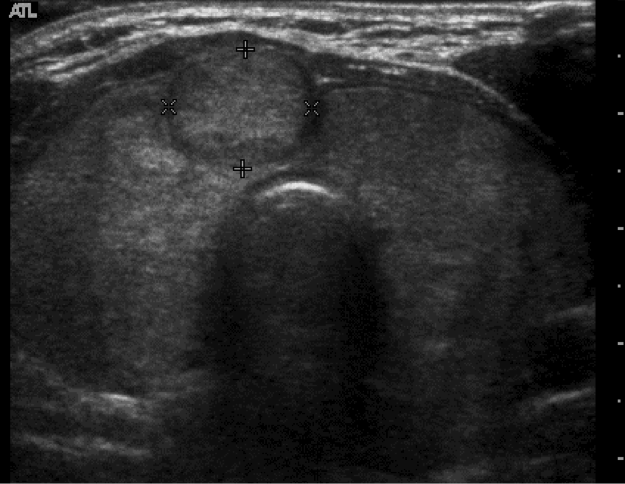

Dx?

Solid nodule